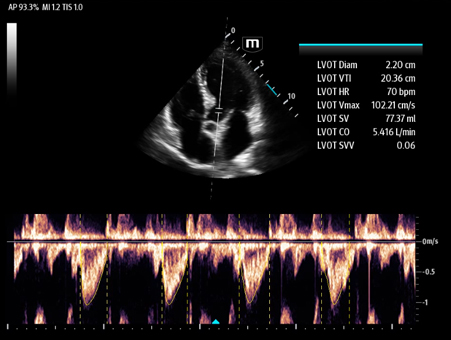

Mindray's Emergency Ultrasound Solutions address clinical challenges through a systemic approach. Those solutions cover the entire emergency care process from pre-hospital rescue and ambulance transport to ER treatment and in-hospital transfer. The versatility of Mindray Ultrasound shaping from Tablet system, Laptop-based system to Handheld Ultrasound system brings up the power of Ultrasound at the point of care. Clinical oriented smart features and protocols assist decisions with confidence.